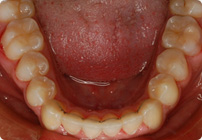

Retenedores: Inferior Fijo

Tiempo de tratamiento: 16 Visitas